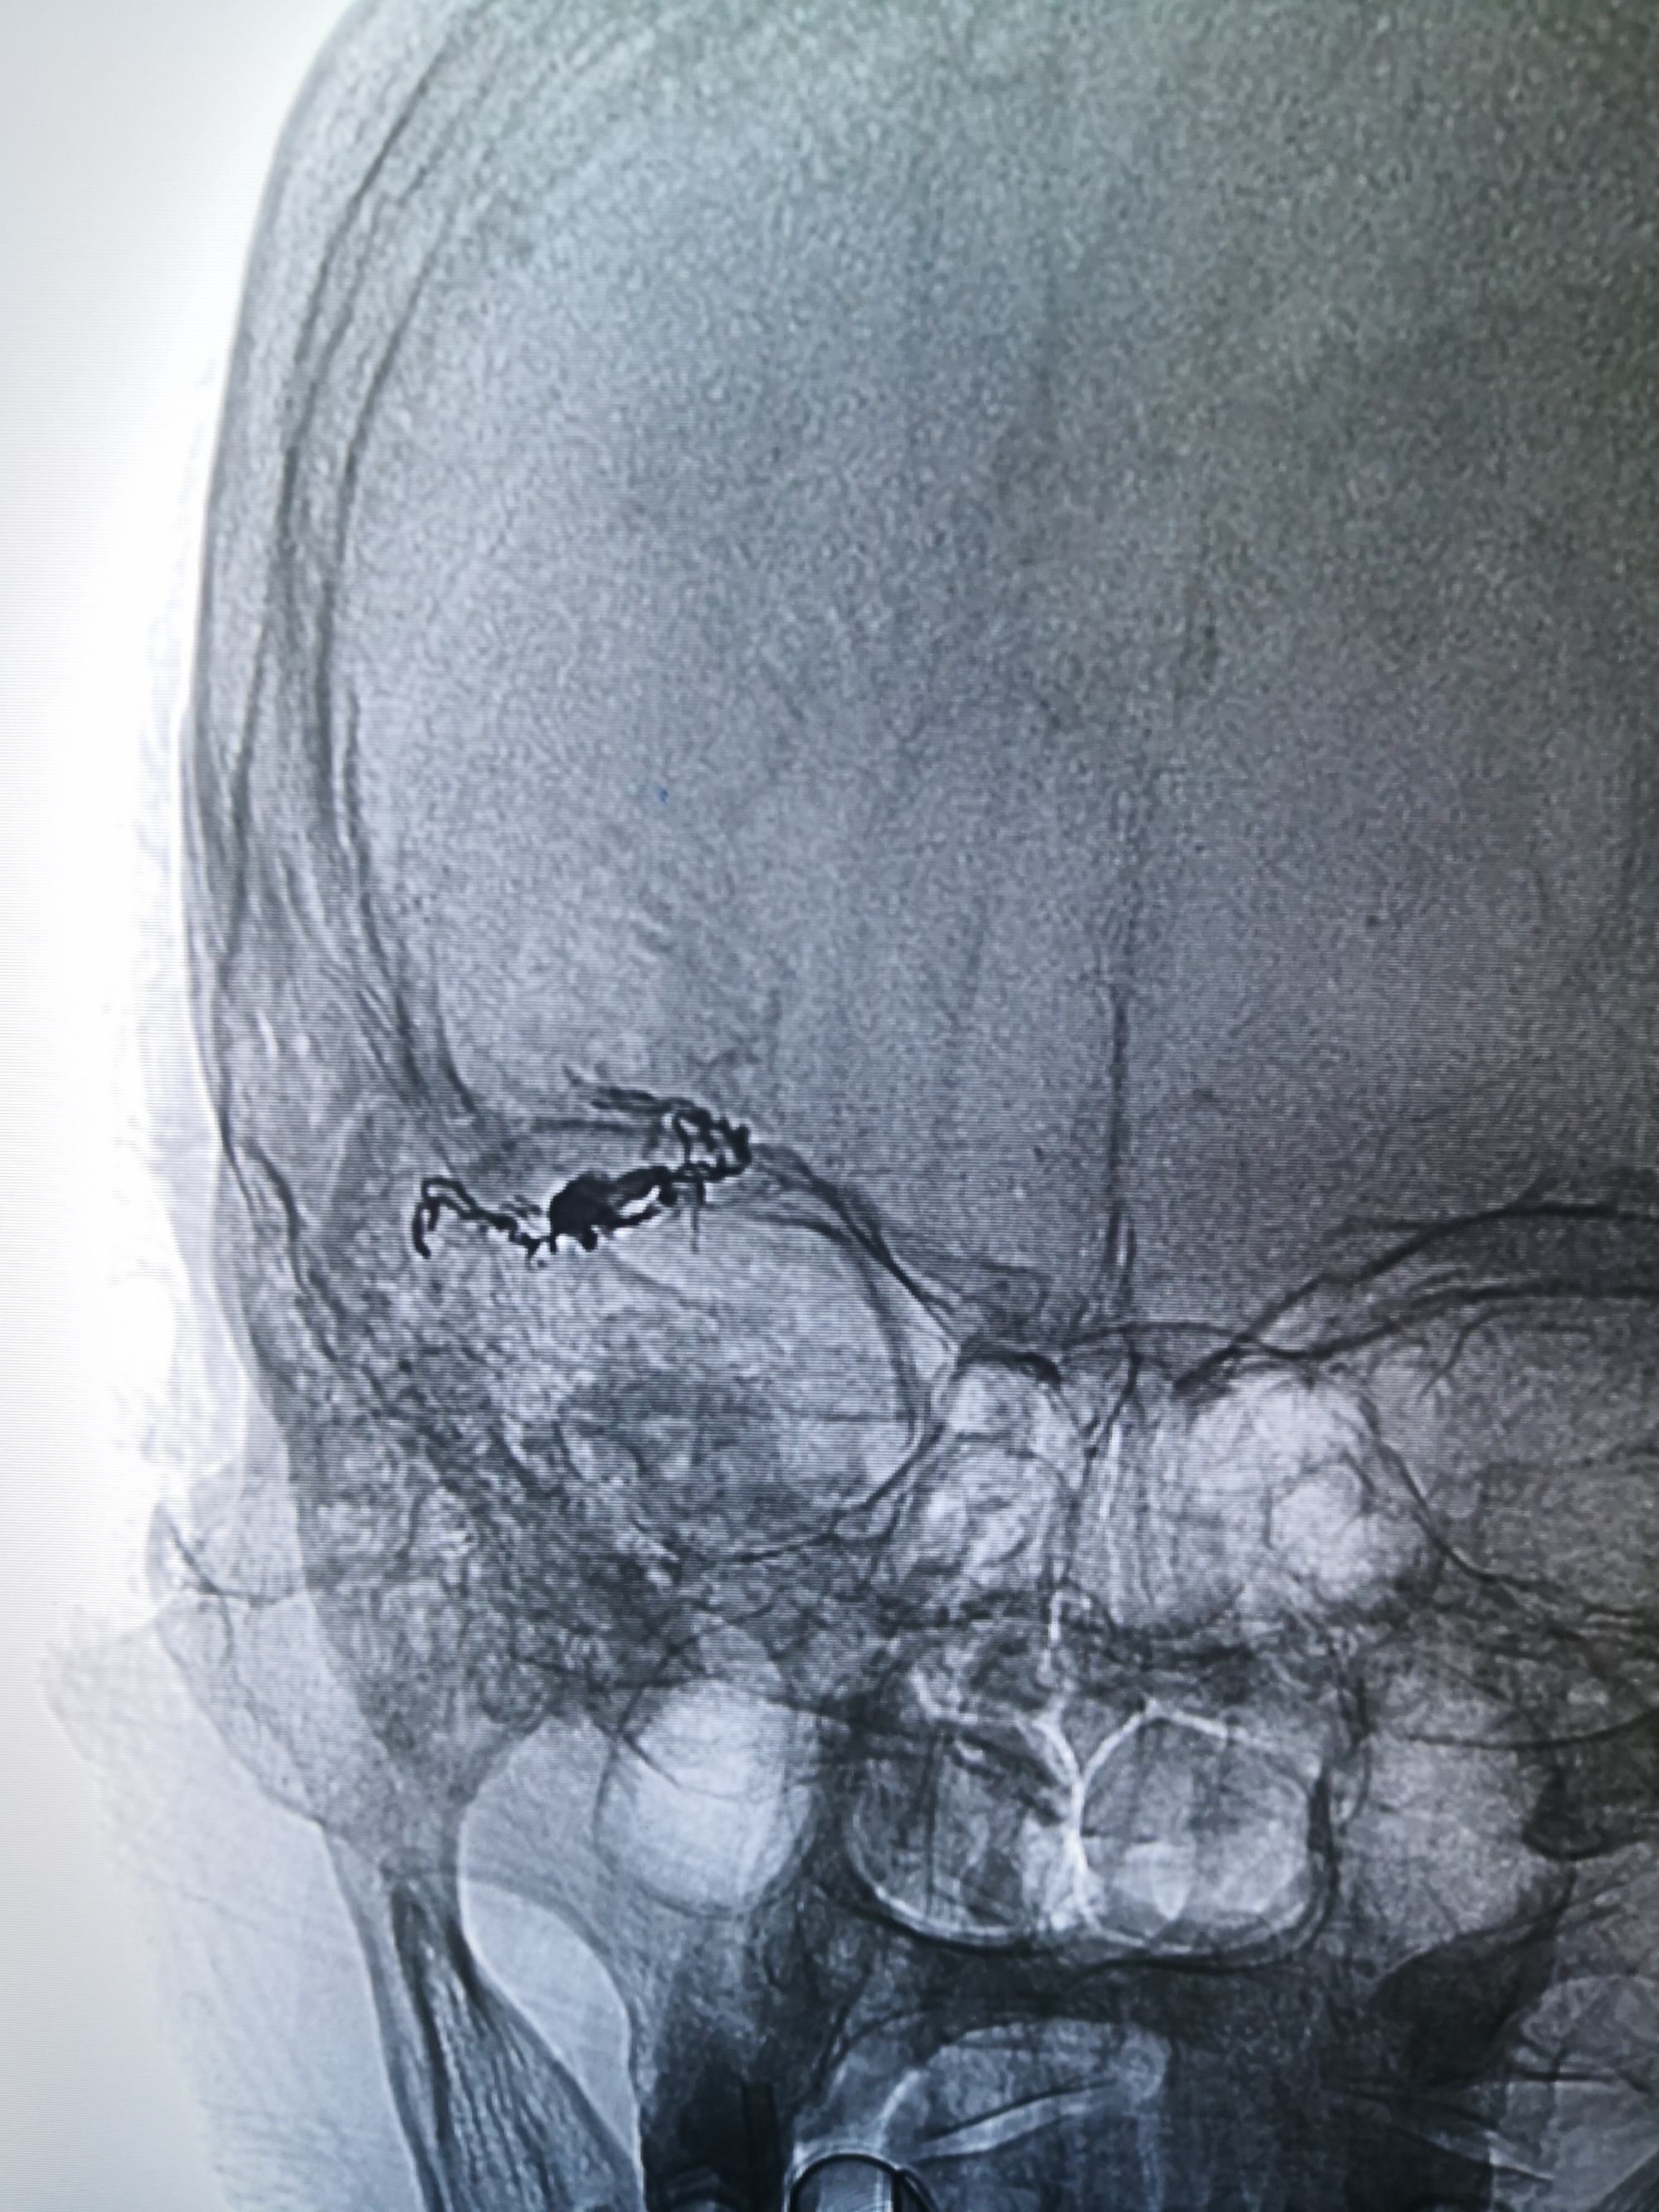

术后,清爽了,瘘口都不在显影,

不减影,看看胶

术后,清爽了,瘘口都不在显影,

不减影,看看胶